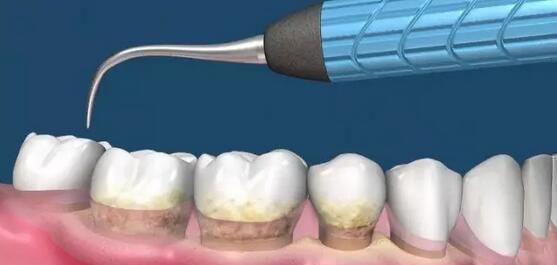

为什么洗牙把牙结石洗掉了,你会觉得牙齿也松动了?

谁敢给我洗牙,我跟谁急!我的牙齿就靠牙石撑着了

为什么医生让我,洗牙,洗牙,赶紧洗牙!

关于“洗牙”的问得最多最奇葩的20个问题!涨知识

医生,洗牙后我牙齿酸软咋回事?